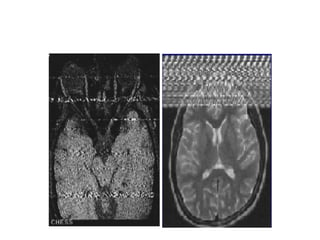

Crisscross or Herringbone Artifacts

• caused

due to a data processing or

reconstruction error.

• Appears

It is characterized by an obliquely oriented

stripe that is seen

throughout the image.

• Eliminated

reconstructing the image again.

Crisscross or HerringboneArtifacts • caused due to a data processing or reconstruction error. • Appears It is characterized by an obliquely oriented stripe that is seen throughout the image. • Eliminated reconstructing the image again.